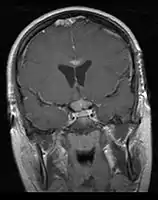

- Mainly located in midline structures, suprasellar region or pineal gland, also basal ganglia and hypothalamus

- Natural spread believed to be along subependymal lining of 3rd and 4th ventricles, leading to intraventricular relapse before spinal dissemination

- Whole ventricular volume: 3rd, 4th, lateral, prepontine cistern

- Involved field volume: pre-chemotherapy volume + clinical margin 1-1.5 cm